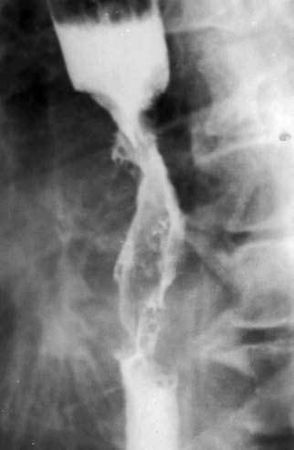

Рис. 41. Рентгенограмма экзофитной опухоли. На рентгенограмме виден дефект наполнения, который более выражен по правой стенке пищевода – контрастное вещество оттесняет растущая в просвет органа опухоль

Экзофитный рак растет преимущественно в просвет органа, образуя при традиционном рентгенологическом исследовании дефект наполнения с непрерывными бугристыми контурами (рис. 41).